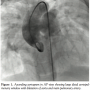

The child was taken up for assessment of PVR and device closure of the APW. The femoral artery and vein were percutaneously cannulated. Unfractionated heparin (100 units/kg) was administered after vascular access was obtained. There was a 20% increase in saturation at the left pulmonary arterial level compared to superior vena cava. She had high pulmonary artery pressures (76/44 mmHg, mean=55 mmHg, 2/3 of systemic pressures), Qp/Qs was 3.5:1 and PVRI was 6·1 Wood units·m2. Ascending aortography demonstrated a large distal APW measuring 14 mm. As the defect was about 6 mm away from coronary ostium, using an atrial septal occluder (which has a 7 mm rim) could have compromised the coronary opening so we decided to use a muscular VSD device. The defect was crossed antegradely from pulmonary artery and an extra stiff Amplatz (360 cm) wire (Cook Medical) was placed in the descending aorta. A 9 Fr long sheath (Cook) was tracked over the wire, across the APW, and was lodged into the descending aorta. An 18 mm muscular VSD device (ShenZhen) was introduced into the long sheath and the distal (left ventricular) disc was opened in the aorta. The device was then retracted towards the defect, and the proximal (right ventricular) disc was opened on the pulmonary arterial side of the defect. The mean PA pressure dropped to 36 mmHg. Appropriate device position was confirmed both by transthoracic echocardiography and angiograms in multiple views. There was no residual flow across and no obstruction to either aortic or pulmonary arterial flow. She was put on oral aspirin for 6 months and her 1-year follow-up showed improved physical growth, no obstruction to aortic or pulmonary arterial flow, and near normalization of PA pressures on 2D echocardiogram.